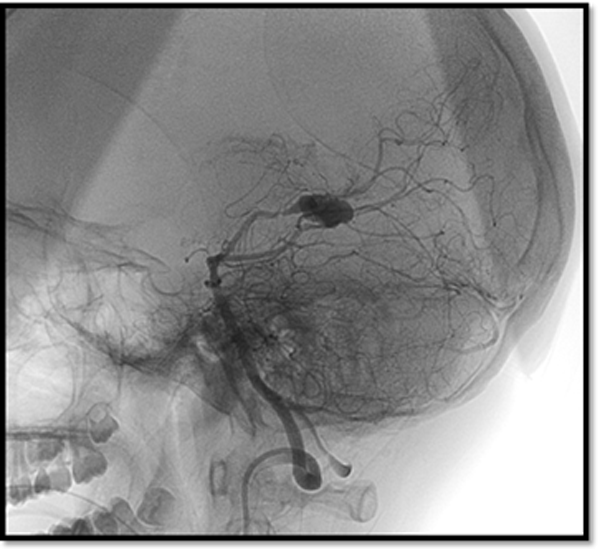

Se efectuó una craneotomía suboccipital lateral con evacuación del absceso cerebeloso. En la evolución, el paciente presentó un hematoma espontáneo secundario a la rotura de un aneurisma fusiforme del segmento P3 de la arteria cerebral posterior, confirmado por angiografía digital. El hallazgo fue interpretado como un aneurisma micótico, por lo que se realizó tratamiento endovascular. La resonancia magnética posterior a la embolización no evidenció aneurisma residual (Figuras 1 y 2).

Figura 1. Angiografía digital diagnóstica de vasos intracraneales. Se evidencia dilatación aneurismática del segmento P3 de arteria cerebral posterior derecha.